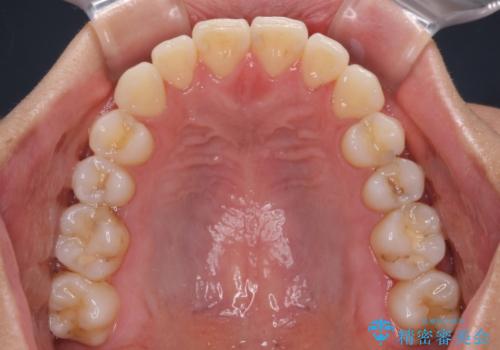

- 前歯のデコボコと奥歯の咬み合わせを気にして来院された患者様です。

右側の奥歯は、上が外側に転位した鋏状咬合を呈しており、前歯のデコボコ改善と並行して咬み合わせを改善していく必要がありました。